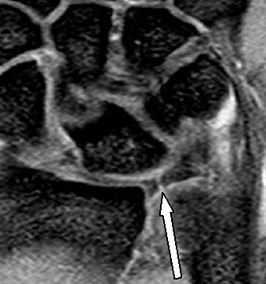

МРТ кисти. Корональная Т1-взвешенная МРТ. Нормальное изображение ладьевидно-полулунной связки. Обозначения: S - ладьевидная кость (scaphoid), L - полулунная кость (lunatum), T- трехгранная кость (triquetrum).

МРТ кисти. Корональная градиентная МРТ. Нормальное изображение полулунно-трехгранной связки. Обозначения: S - ладьевидная кость (scaphoid), L - полулунная кость (lunatum), T- трехгранная кость (triquetrum).